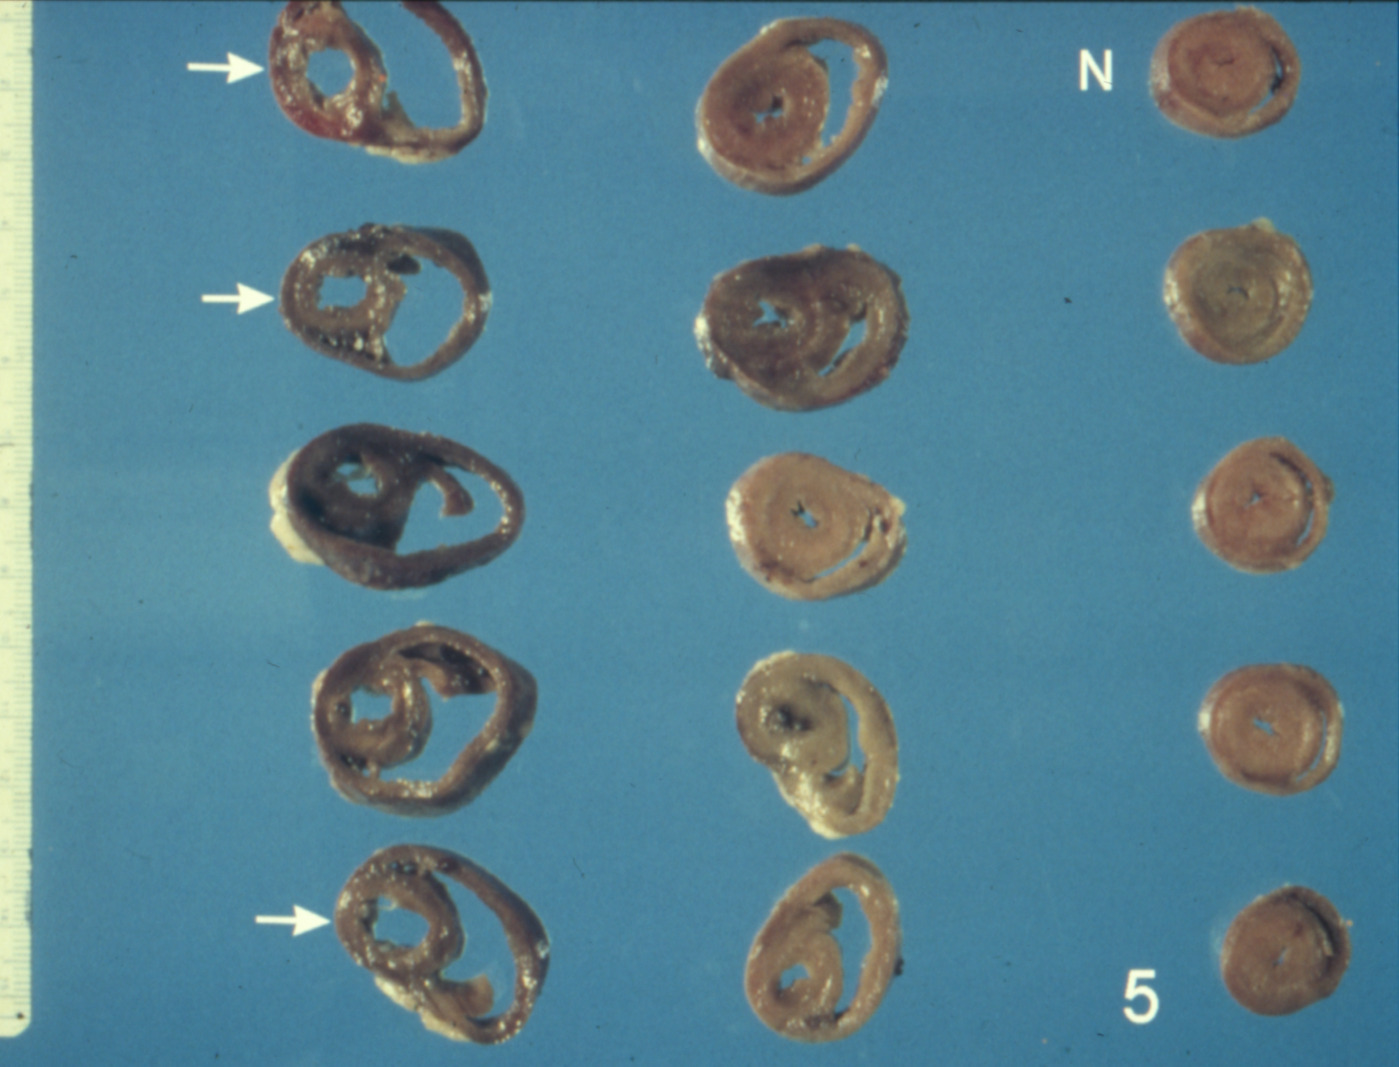

Ascites syndrome in meat-type chickens (slide study set no. 23)

Chickens--Diseases Ascites

Slide Study Set #23, Ascites Syndrome in Meat-Type Chickens (includes 27 color slides), 2001